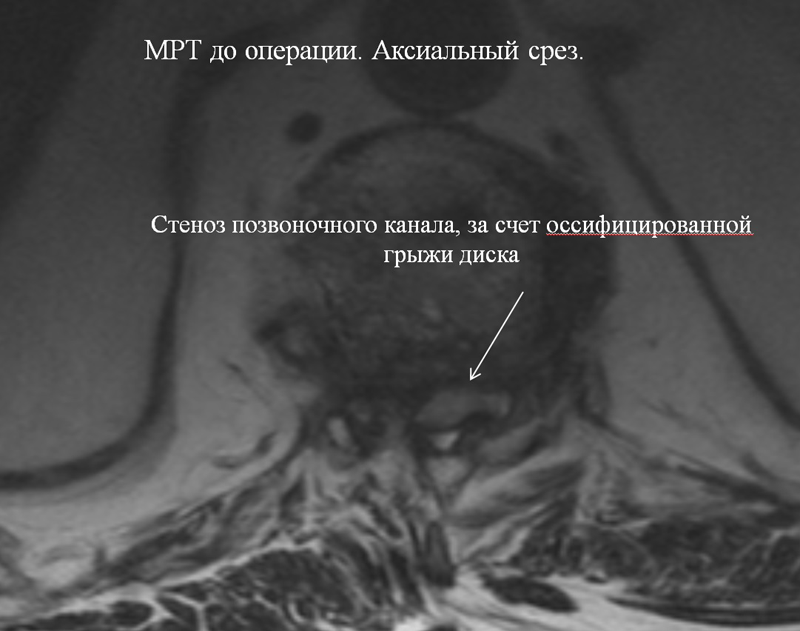

Впервые в России выполнена робот-ассистированная операция с использованием системы «Da Vinci» на грудном отделе позвоночника по поводу оссифицированной грыжи межпозвонкового диска с компрессией спинного мозга